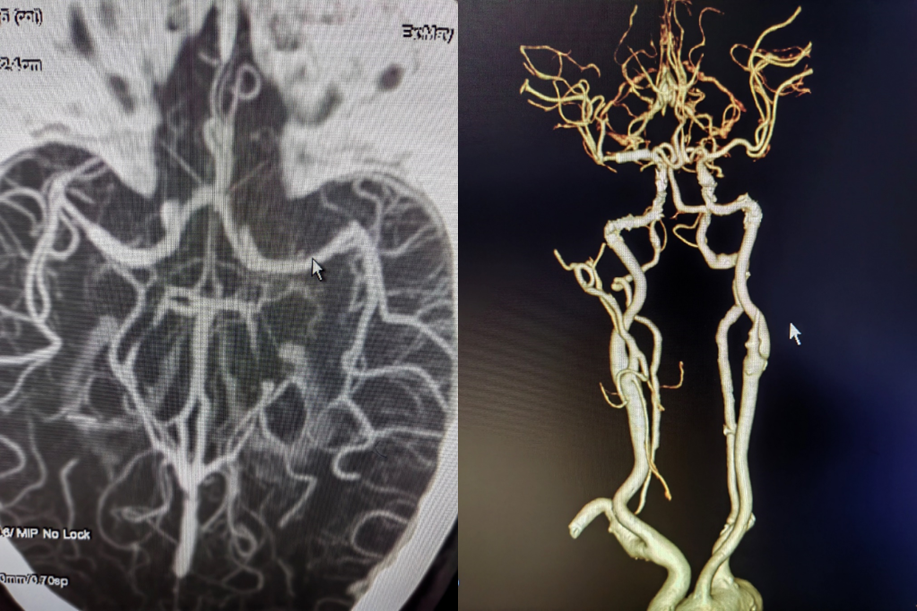

入院影像检查

导丝怎么扩【载药时代 球扩天下】NOVA DES®颅内药物洗脱支架在大脑中动脉重度狭窄的应用二例!_https://www.jmylbn.com_新闻资讯_第3张

MRI+DWI

重要影像结论:右侧放射区、右侧基底节区、左侧额叶近大脑镰处多发急性梗死。

导丝怎么扩【载药时代 球扩天下】NOVA DES®颅内药物洗脱支架在大脑中动脉重度狭窄的应用二例!_https://www.jmylbn.com_新闻资讯_第4张

MRI  T2相

重要影像结论:右侧颈内动脉岩骨段管腔内不清晰,眼动脉段远端管腔较对侧明显缩小。

导丝怎么扩【载药时代 球扩天下】NOVA DES®颅内药物洗脱支架在大脑中动脉重度狭窄的应用二例!_https://www.jmylbn.com_新闻资讯_第5张

导丝怎么扩【载药时代 球扩天下】NOVA DES®颅内药物洗脱支架在大脑中动脉重度狭窄的应用二例!_https://www.jmylbn.com_新闻资讯_第6张

重要影像结论:右侧ICA起始部急性闭塞,前交通动脉、后交通动脉未开放。